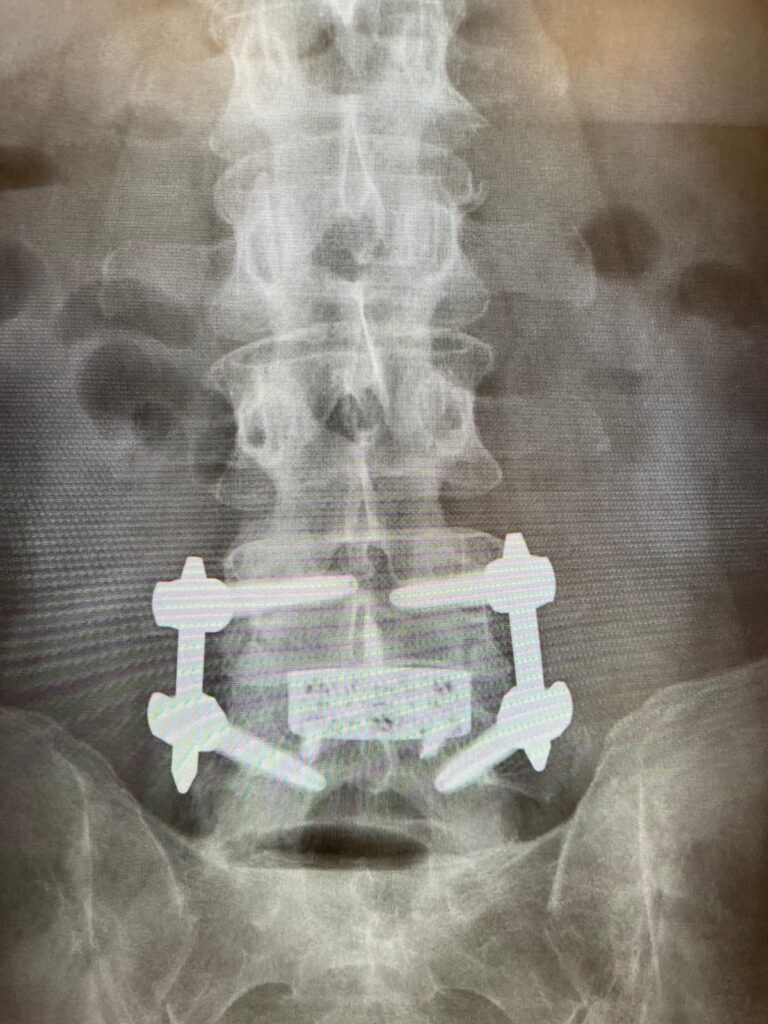

This patient underwent a 360° minimally invasive spinal fusion (MISS) to treat spondylolisthesis—performed entirely in an ambulatory surgery center. Traditionally, this type of procedure requires hospitalization and an extended recovery period. However, by leveraging advanced minimally invasive techniques, Dr. Peloza was able to perform the fusion with minimal disruption to tissue and surrounding structures.

Less than 20 hours after surgery, the patient returned to the office walking comfortably, showing exceptional early mobility and virtually no visible signs of surgical trauma.

This case underscores how advancements in MISS technology and outpatient spine care are redefining expectations for recovery—proving that complex spinal instability can be effectively treated in an ASC environment with outstanding results.